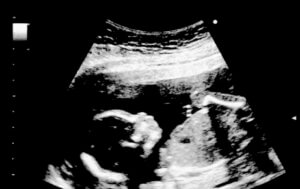

임신 18주 차에 도달하면 태아의 크기는 14cm가량에 도달하고 체중은 184~198gram가량이 된다. 이 작은 아기의 움직임은 갈수록 더욱 활발해진다.

초음파 촬영 시 아기가 팔, 다리를 쭉 뻗거나 움츠리고 있는 모습을 관찰할 수 있다. 또한, 태아가 무언가를 삼키는 것처럼 입을 벌렸다 다무는 모습을 볼 수 있을 수도 있다.

태아 피부는 투명해서 혈관이 눈에 보인다. 눈썹이나 속눈썹 또한 나타나고 이때 아이의 눈과 귀의 위치가 결정된다. 초음파를 통해 예비 부모는 아기가 손가락을 빠는 모습을 볼 수도 있다.